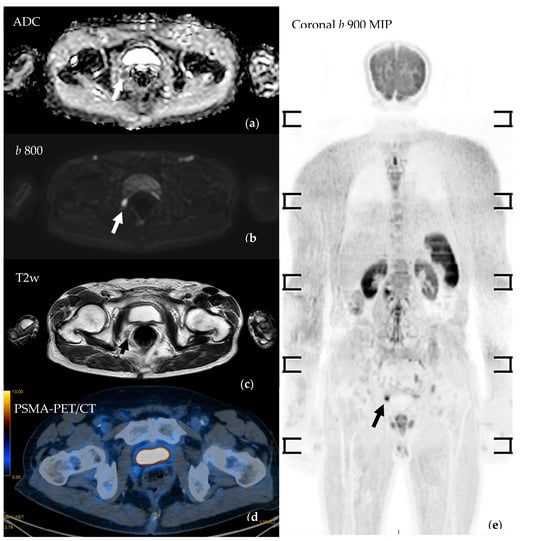

3.4. Imaging Features of Metastatic PC in WB-MRI

3.4.1. Evaluation of Bone Metastases with WB-MRI

3.4.2. Assessment of Nodal Disease

3.4.4. Assessing Local Disease and Biochemical Recurrence